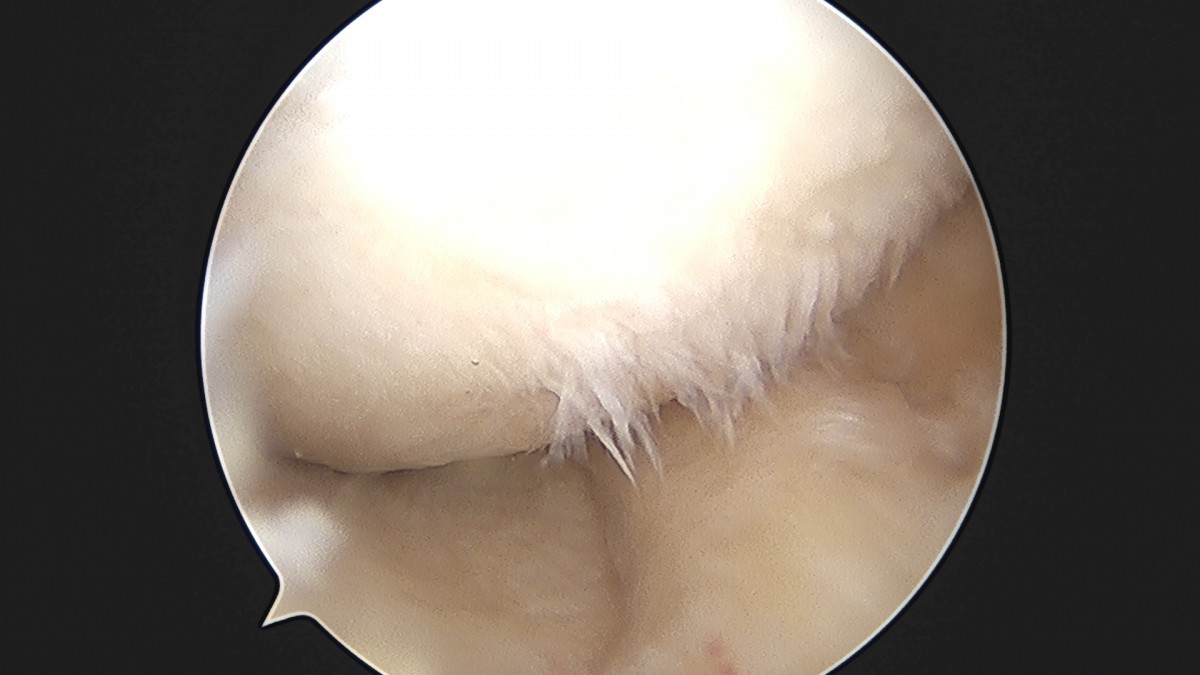

이재상원장님 무릎 반월상 연골판 절제술 박민O 환자

dae765e4d9ac96aee867c9d6292d8784_1758005184_7009.jpg